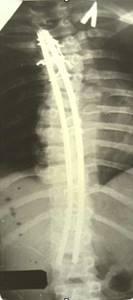

| Динамический корректор. Результат на 2-е сутки после операции |

| Больной З-ч. 13 лет Сколиотическая деформация II степени грудного отдела позвоночника. Рентгенограмма позвоночника до операции |

Результат оперативного лечения. Коррекция 100% |